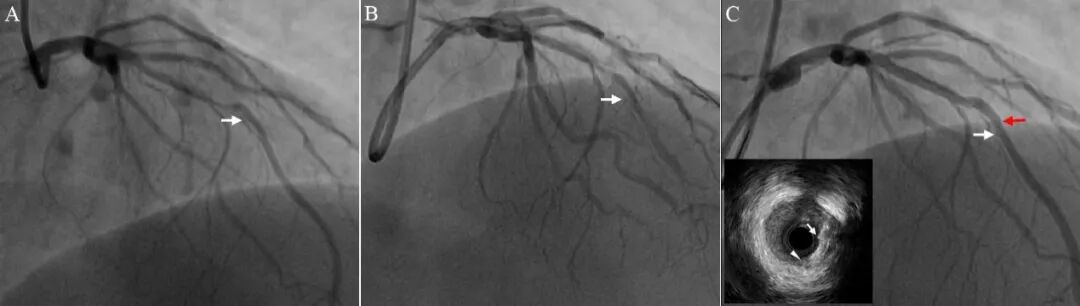

图3 支架张力性移位(成角病变)。前降支中段长病变伴成角(A,白色箭头为拟放支架位置,间隔支发出处)。支架初始位置过远达至前降支远段,回拉支架,远端定位良好(B, 白色箭头为支架远端位置,齐平间隔支发出处)。支架释放时向近端移位(C,白色箭头为支架原定位处,红色箭头为支架实际释放处)。未覆盖区域IVUS检查发现钙化小结(箭头)和可疑夹层(三角)。